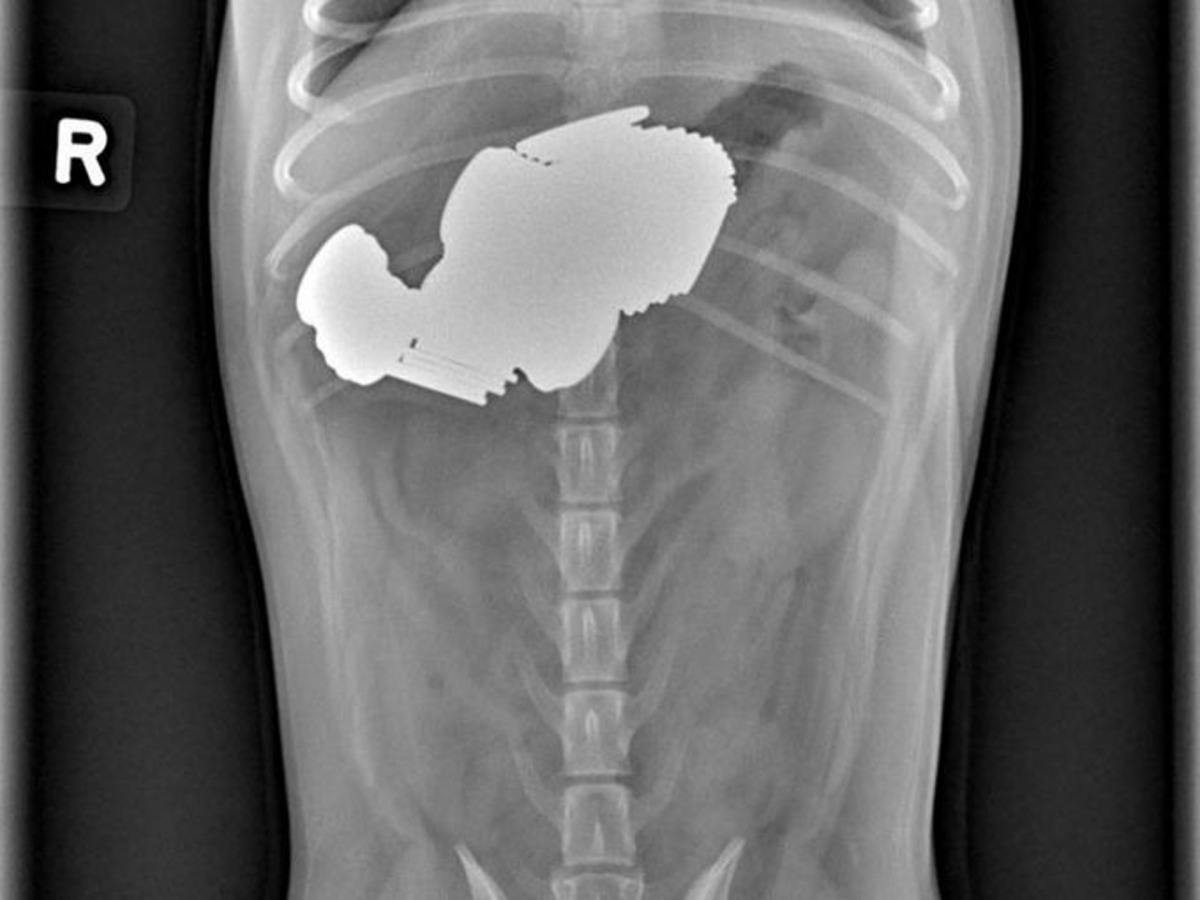

令人驚訝的當然不止上述的小青蛙,來自佛羅里達州一隻6歲狗狗馬利(Marley)亦成為是次比賽的焦點!事情的緣由是狗狗看見主人放下插滿蔬菜及肉肉的串燒燒烤針後,竟趁著主人走開時吃下其中一支針!當主人回頭看時才驚覺Marley已將燒烤針吞下。負責診治狗狗的獸醫高斯曼(Tim Gossman)表示,主人起初都不敢相信毛孩吞下了燒烤針,「後來我做了X光檢查向他證明,最後真的看到燒烤針清晰地出現在狗狗的胃內。」